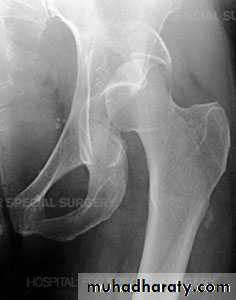

Traumatic anterior hip dislocation:Mechanism :

Road traffic accident ,miner, building laborer who is leg wide .

knees straight .

Back bent forward.

Clinically:

O\ELeg external rotation.

Abducted and slightly flexed.

Bulging head seen laterally and also feel.

Hip movement impossible.

Neurovascular examination necessary.

Radiological examination:

Hip dislocated either superior, inferior in relation to the acetabulum.Treatment: